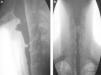

A) Lateral projection of the barium swallow: stricture in the proximal region of the upper esophageal sphincter. B) AP projection of the barium swallow: medial stricture in the proximal region of the upper esophageal sphincter. The proximal part of the stricture is dilated and the inferior part of the stricture has irregular walls.

A 30-year-old man with a past history of epidermolysis bullosa since childhood, with several affected first-grade relatives, presented with generalized dermatologic involvement (figs. 1A and B) that intensified over the last 5 years. He was referred to the gastroenterology service with oropharyngeal dysphagia of 2-year progression and a 10-kg weight loss related to reduced food intake due to the swallowing alteration. He had dysphagia with solid food intake from the onset of the condition. As part of the clinical evaluation, the Volume-Viscosity Swallow Test (V-VST) was carried out: he tolerated liquids in small amounts at the time of the assessment. The evaluation protocol included endoscopy, which identified a stricture 13cm from the upper dental arcade that did not allow the passage of the endoscope. A barium swallow revealed a proximal stricture of the upper esophageal sphincter (figs. 2A and B). The treatment proposal was a modification in relation to food texture and caloric intake and non-endoscopic percutaneous gastrostomy for later dilation.